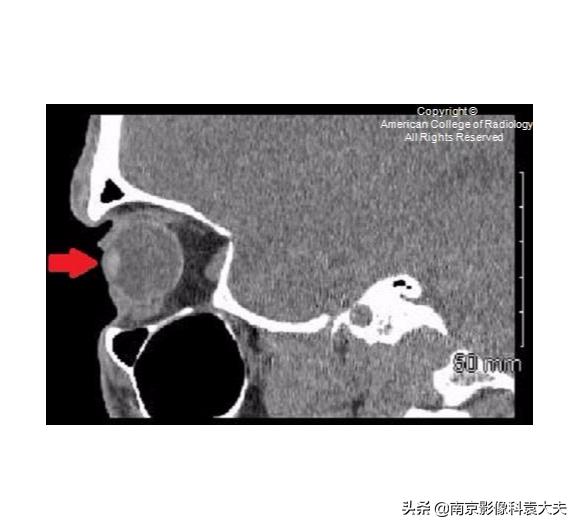

右眼矢状位非对比增强CT(平扫)显示前房(箭头)塌陷。这可以在角膜裂伤的情况下看到。

穿透性创伤或裂伤可能损害前房,使虹膜脱出进入前房。在CT图像上,前房液体的体积减少导致前房的前后径缩小。